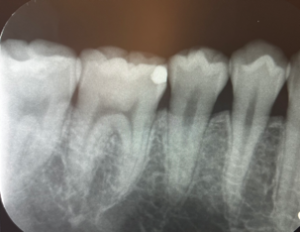

その後エックス線をよく確認したところ、歯と歯の間の複数箇所に虫歯があり、プラスチックで治療した痕(白い部位)がありました。

プラスチックは茶色く変色し、縁は黒ずんでいます。歯と歯の間は、凹んでいるためフロスも通しづらい状態でした。さらに詳しく調べるために口腔内エックス線も撮影し、詰め物の大きさを確認することにしました。